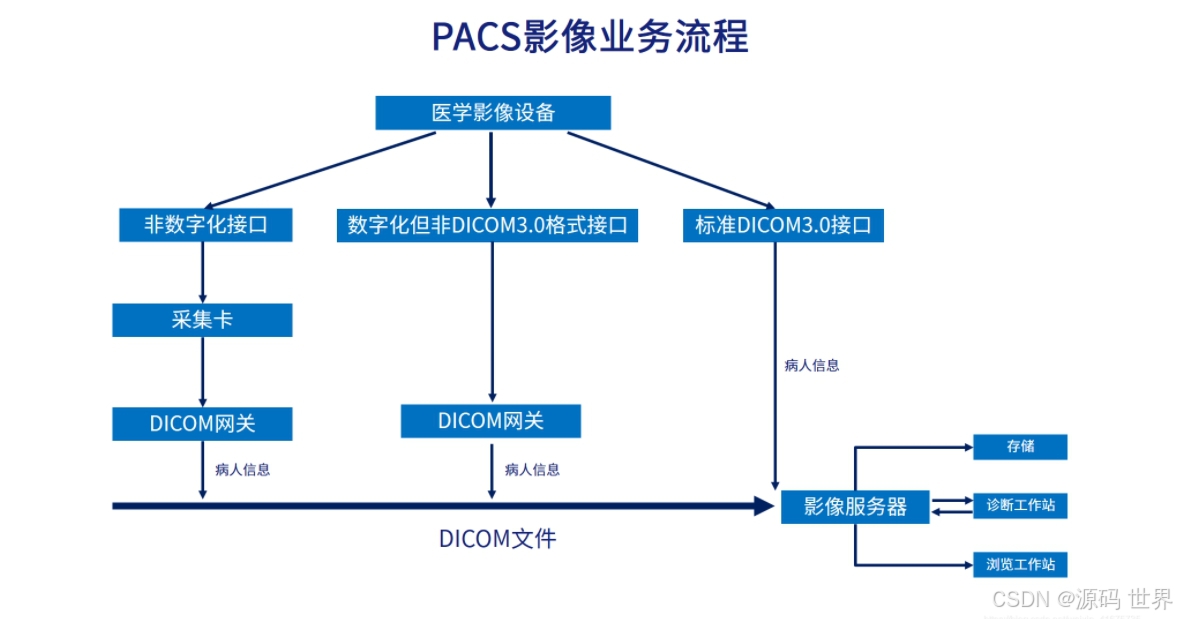

影像数据的管理:各种DICOM3.0和非DICOM3.0接口的设备接入,海量数据存储,多级存储架构、数据的多种压缩管理和移动存储介质的支持。

● PACS 业务流程

注重影像中心现有工作流程,结合不同影像检查特点,在遵循PACS基本规律的前提下,工作流程的设计尽量符合影像中心现有工作特点,同时进行优化设计。在影像获取、存储、显示及处理过程中,以保证诊断应用为质量为标准。考虑到诊断过程的实用性要求,满足快速调影像资料。